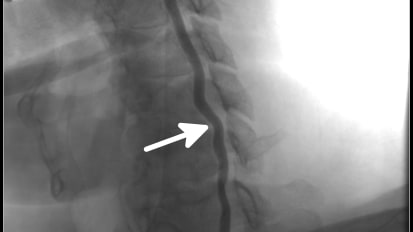

Performing a Minimally Invasive Approach for Spinal Tumor Resection

Johns Hopkins neurosurgeons eschew open surgery to help a patient with metastatic breast cancer quickly return to her active lifestyle.